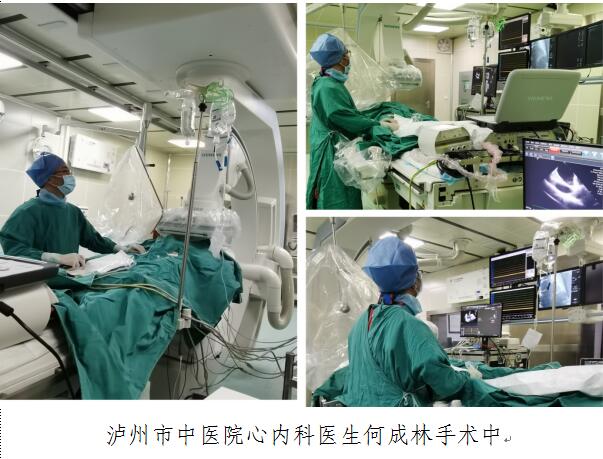

如果把心脏比喻成一个“电器”,那“维修”这个电器的医生就好比是一个电工。当电器出现故障时,由于电器内部结构复杂,一旦这个电工没有处理妥当,这个人可能就“哦豁了”,但如果这个电工长了一双“透视眼”,那维修结果肯定就大不相同。这不,最近,泸州市中医院就运用“透视眼”技术成功救治一位6...

如果把心脏比喻成一个“电器”,那“维修”这个电器的医生就好比是一个电工。当电器出现故障时,由于电器内部结构复杂,一旦这个电工没有处理妥当,这个人可能就“哦豁了”,但如果这个电工长了一双“透视眼”,那维修结果肯定就大不相同。这不,最近,泸州市中医院就运用“透视眼”技术成功救治一位6...